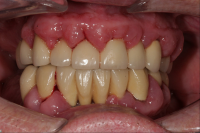

Parodontal stabilitet karakteriseras av framgångsrik behandling genom kontroll av lokala och systemiska riskfaktorer, vilket resulterat i

• minimal blödning vid sondering (BVS < 10 % av tandytorna)

• fickdjup < 3 mm

• ingen progressiv parodontal nedbrytning/vävnadsförlust

• optimal förbättring i övriga kliniska parametrar hos behandlad parodontitpatient.